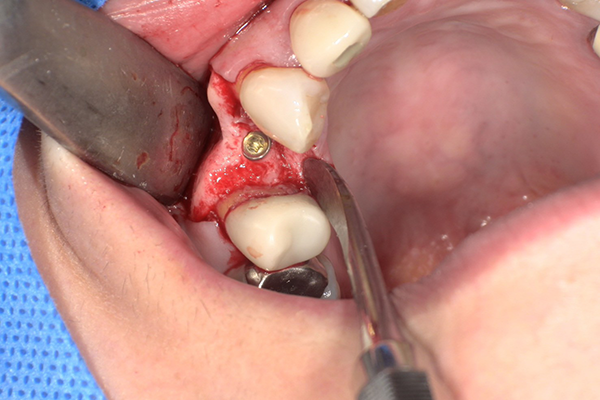

①メスを用いてインプラント体埋入部に歯槽頂切開を加える

②フィクスチャーに装着してあるカバースクリューを外す

この時、カバースクリューが骨などの硬組織に覆われてしまっている場合、フィクスチャーを損傷しないように、慎重に除去します。

③フィクスチャーにヒーリングアバットメントを装着し縫合する